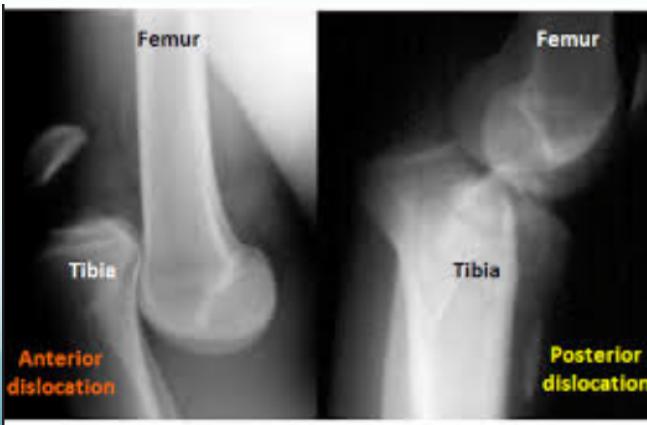

Knee (Tibiofemoral) Dislocation

X-ray Findings:

- Dislocation

- Fractured tibial spine (cruciate ligament avulsion)

- Avulsion fibular styloid (collateral ligament avulsion)